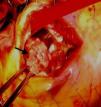

Transthoracic and transesophageal echocardiography revealed a restrictive subpulmonary ventricular septal defect (VSD) and infundibular pulmonary stenosis (Figure 1 and Video 1), with multiple vegetations related to the VSD involving the right coronary cusp of the aortic valve and protruding into the right ventricular outflow tract (RVOT) (Figure 2 and Videos 2 and 3). Vegetations were also observed adhering to the pulmonary valve and the pulmonary artery wall, probably due to jet lesion (Figure 3 and Video 4). A diagnosis of infectious endocarditis was made and the patient underwent surgery for removal of the vegetations (Figure 4), VSD closure, enlargement of the RVOT and pulmonary valvuloplasty without use of prosthetic material. His postoperative course was good, with no significant residual lesions, and there were no signs of heart failure or recurrence of endocarditis after two years of follow-up.

This case is an example of congenital heart disease with multiple defects with an indolent course that was manifested by aggressive infectious endocarditis involving the left and right valves and with high embolic risk. It also highlights the success of surgical intervention to simultaneously remove the infected material and repair the congenital defects.